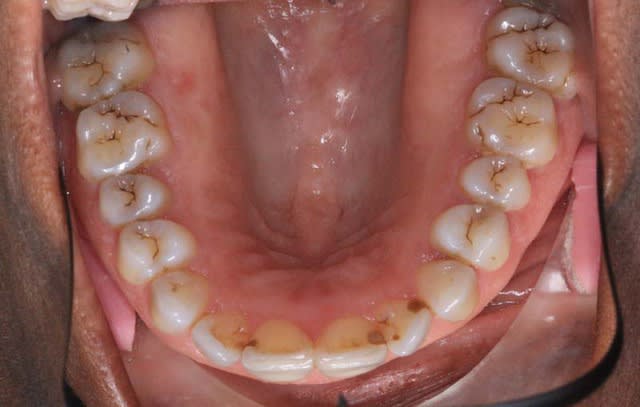

il n'y a rien qui vous choque dans la forme d'arcade Md. ?

@+ Bjc.

> il n'y a rien qui vous choque dans la forme d'arcade Md. ?

>

> @+ Bjc.

qu est ce que tu veux dire ? sa dissymétrie ? le U un peu déformé qu'elle exprime ?

Des acracdes imparfaites comme ça ne me suffisent pas à poser un diag.

Si ce n'est pas la différence entre l’arcade en U et l’arcade plus harmonieuse en haut et bien je donne ma langue au chat ou l'absence de symétrie.....

"""Des acracdes imparfaites comme ça ne me suffisent pas à poser un diag."""

et l'exostose complète palatine au Max. Sup. ?